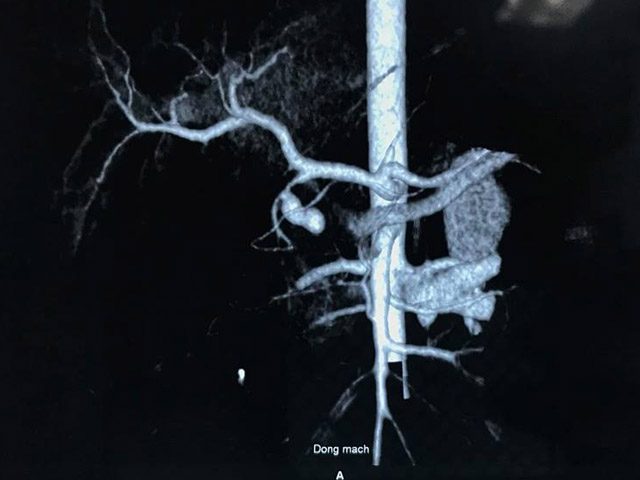

Kết quả hội chẩn toàn viện bệnh nhân đã đượcchẩn đoán: nhồi máu cơ tim cấp có biến chứng ngừng tuần hoàn, suy đa tạng, xuất huyết tiêu hóa có chỉ định chụp và đặt stent mạch vành. Tuy nhiên do tình trạng quá nặng, đặc biệt là xuất huyết tiêu hóa nên BN được chuyển đến khoa Hồi sức tích cực ngày 23/11/2018.

Sau khi hội chẩn với lãnh đạo Viện tim mạch và khoa Tiêu hóa, các bác sĩ thống nhất chẩn đoán: nhồi máu cơ tim cấp có biến chứng ngừng tuần hoàn, suy đa tạng, xuất huyết tiêu hóa/ van tim nhân tạo, tăng huyết áp. Hướng xử trí: tim phổi nhân tạo (ECMO), can thiệp mạch vành để tránh nguy cơ ngừng tuần hoàn trong quá trình can thiệp.

Đến 03/12, bệnh nhân xuất hiện tình trạng sốc: huyết áp không đo được, nhịp tim nhanh, suy hô hấp tăng với nhiều máu chảy ra từ phổi, siêu âm tim thấy hình ảnh kẹt van cơ học do huyết khối bám van tim. Bệnh viện đã hội chẩn toàn viện gồm các chuyên gia đầu ngành và quyết định dùng thuốc tiêu sợi huyết trước, nếu không cải thiện thì phải phẫu thuật. Bác sĩ Hải có chỉ định mổ thay van hai lá sinh học.